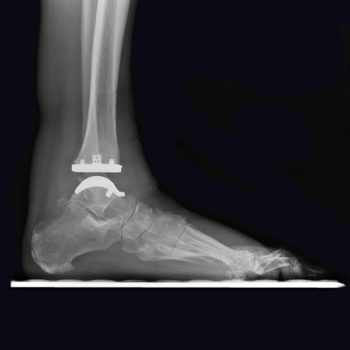

Eine neue Perspektive für das Sprunggelenk

Vantage Sprunggelenk Merkmale und Vorteile

Basierend auf einer firmeneigenen CT-Rekonstruktions-studie wurde die tibiale Komponente so gestaltet, dass eine anatomische kortikale Abdeckung gewährleistet und die fibulare Artikulation ungehindert möglich ist.1,2 Während sich die kurvierte Talus-Komponente der trabekulären Knochenstruktur des Talus anpasst, um inhärente Stabilität zu erreichen, wird die primäre Stabilität bei der flach geschnittenen Talus-Komponente durch einen Press Fit Hohlzapfen und die peripheren Plasmazapfen gewährleistet.

Der Radius der Krümmung auf der Unterseite der Talarkomponente basiert auf Studien, die die Wirkung der Arthrose auf den Talus untersuchten. Das spezifische Design entspricht der krankheitsbedingten Oberflächenveränderung und kann so die erforderliche Menge an Talarresektion reduzieren.2